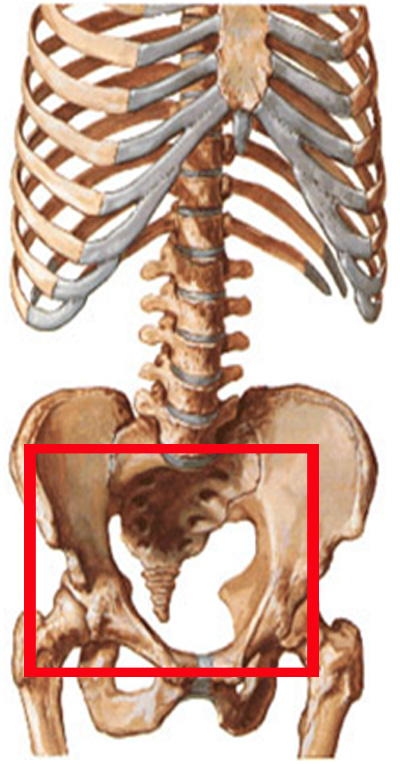

Крестец – одна из главных составляющих тазовой поясничной области скелета человека. Именно на эту часть приходятся практически все нагрузки, которые приходятся на тазовые суставы. Нагрузки со стороны позвоночника проходят на крестцово-подвздошные сочленения.

Перелом крестца зачастую возникает при падании на ягодичную часть или при прямом нанесении травмы. Реже, но все же также может быть причиной и сдавление тазовой кости в переднезаднем направлении. Каждый пятый случай получения травмы такого рода является поперечным перелом крестцовой кости. При этом линия перелома, чаще всего, располагается ниже, чем сочленения крестцово-подвздошного типа. Если же линия выше, то это уже оскольчатый перелом.

Один из основных симптомов перелома крестца – это сильные, непрерывные боли в районе крестца. Симптомами тяжелого перелома также могут сопровождаться кровоизлияниями. При осмотре врач обнаружит припухлость в этом районе и обязательно назначит специальное обследование, которое или подтвердит возможный диагноз, или же опровергнет его. Главный метод диагностики такого перелома – это рентгенография, которая выполняется сразу в двух проекциях.